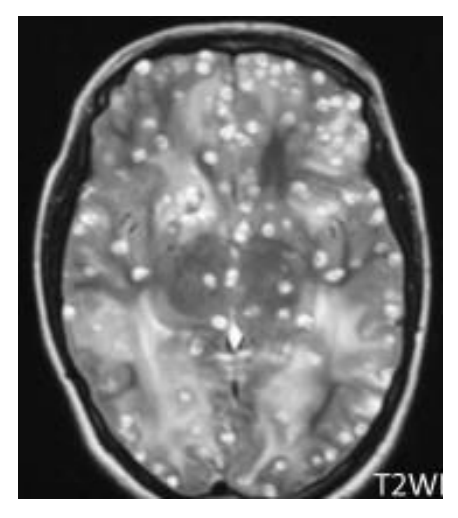

При исследовании головного мозга пациент-X, обратившегося к невропатологу по поводу головных болей, головокружения и нарушения речевых функций, обнаружены многочисленные образования овальной формы, представленные на иллюстрации ниже.

Пациент-X, мужчина 46 лет, проживает в пригороде районного центра, работает фермером. Проанализируйте фотоколлаж, представленный ниже и определите паразита или его фрагмент, одна из стадий которого обнаружена в головном мозге. Выберите номер определенного вами паразита или его фрагмента.